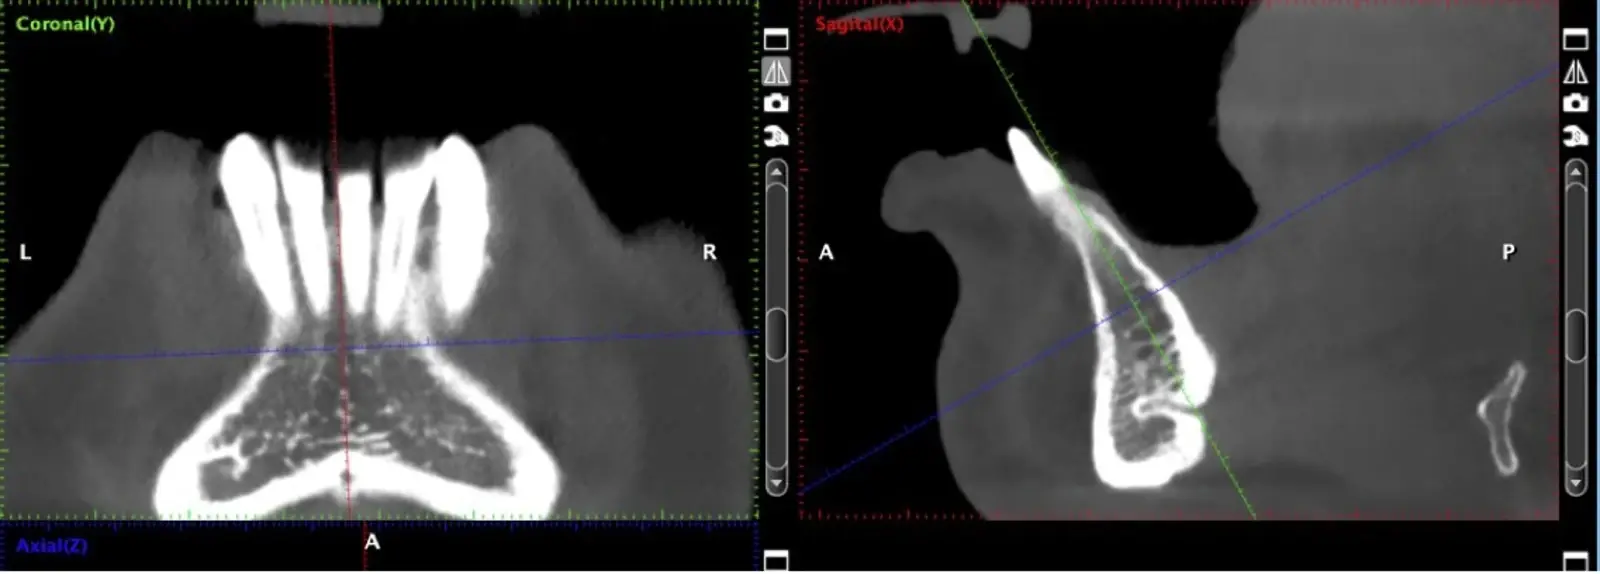

Si la zona donadora es la sínfisis mentoniana, se deben tomar en cuenta los límites de seguridad para la extracción del injerto, que son 5 mm alejado de los ápices, y 5 mm alejado del agujero mentoniano (Figuras 2 y 3).

Figura 2. Evaluación de la tomografía computarizada donde se observa la presencia de un conducto vascular de riesgo a ser considerado.